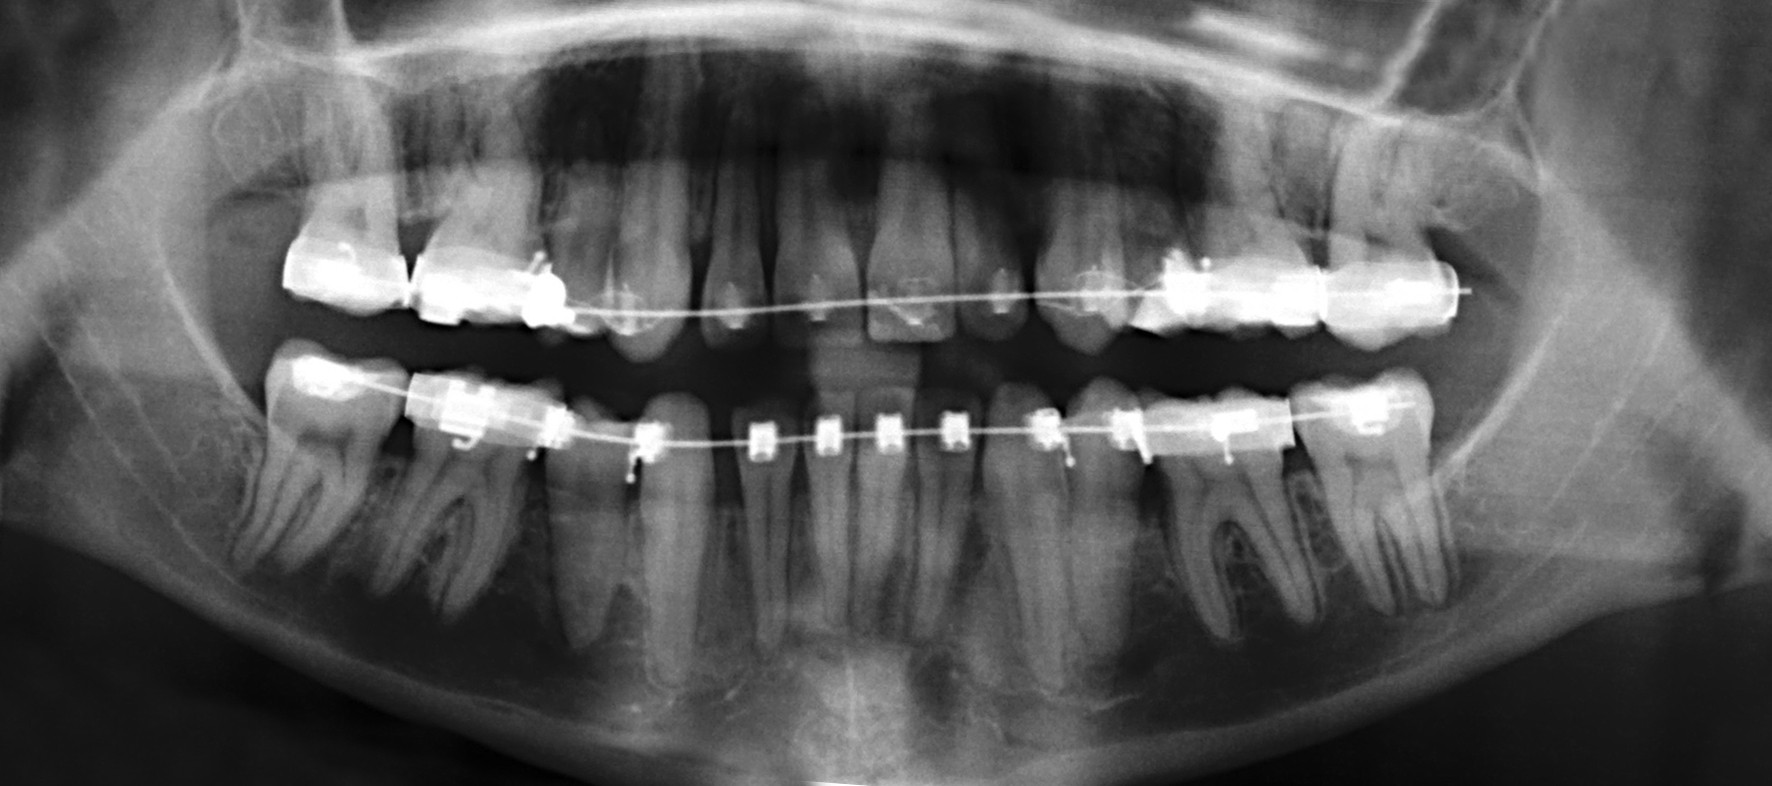

Dan Counihan presents two orthodontic management cases of the unilaterally missing upper first pre-molar.